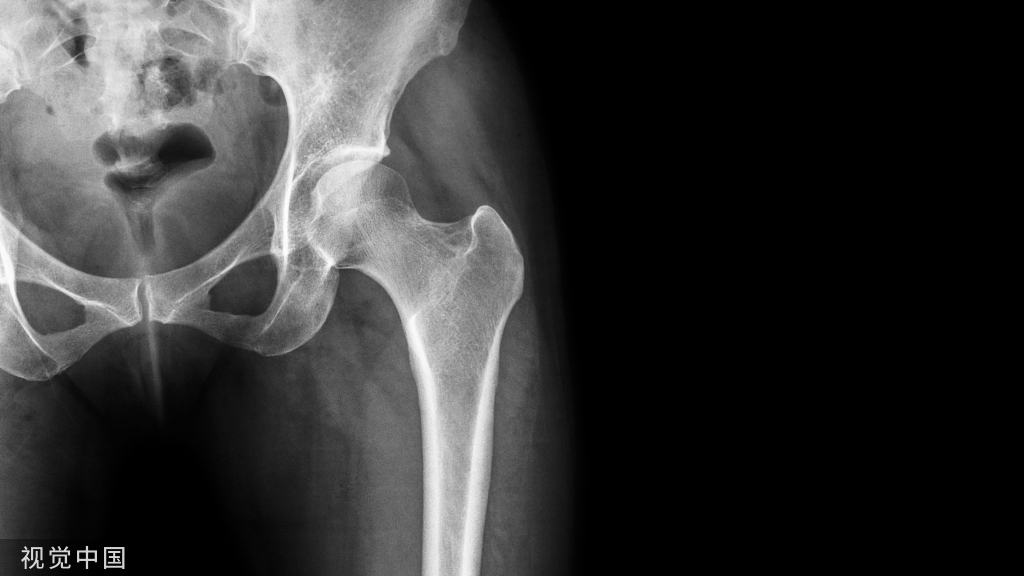

髋部骨折患者发生新冠肺炎的死亡率及相关危险因素!

髋部骨折仍然是一个重要的公共卫生问题,是老年人进行紧急麻醉和手术的最常见原因。新冠肺炎大流行在几个方面影响了髋部骨折的护理。已经有充分的国际证据表明新冠肺炎对髋部骨折患者的直接影响,表明并发新冠肺炎感染增加了严重并发症和死亡率的风险。